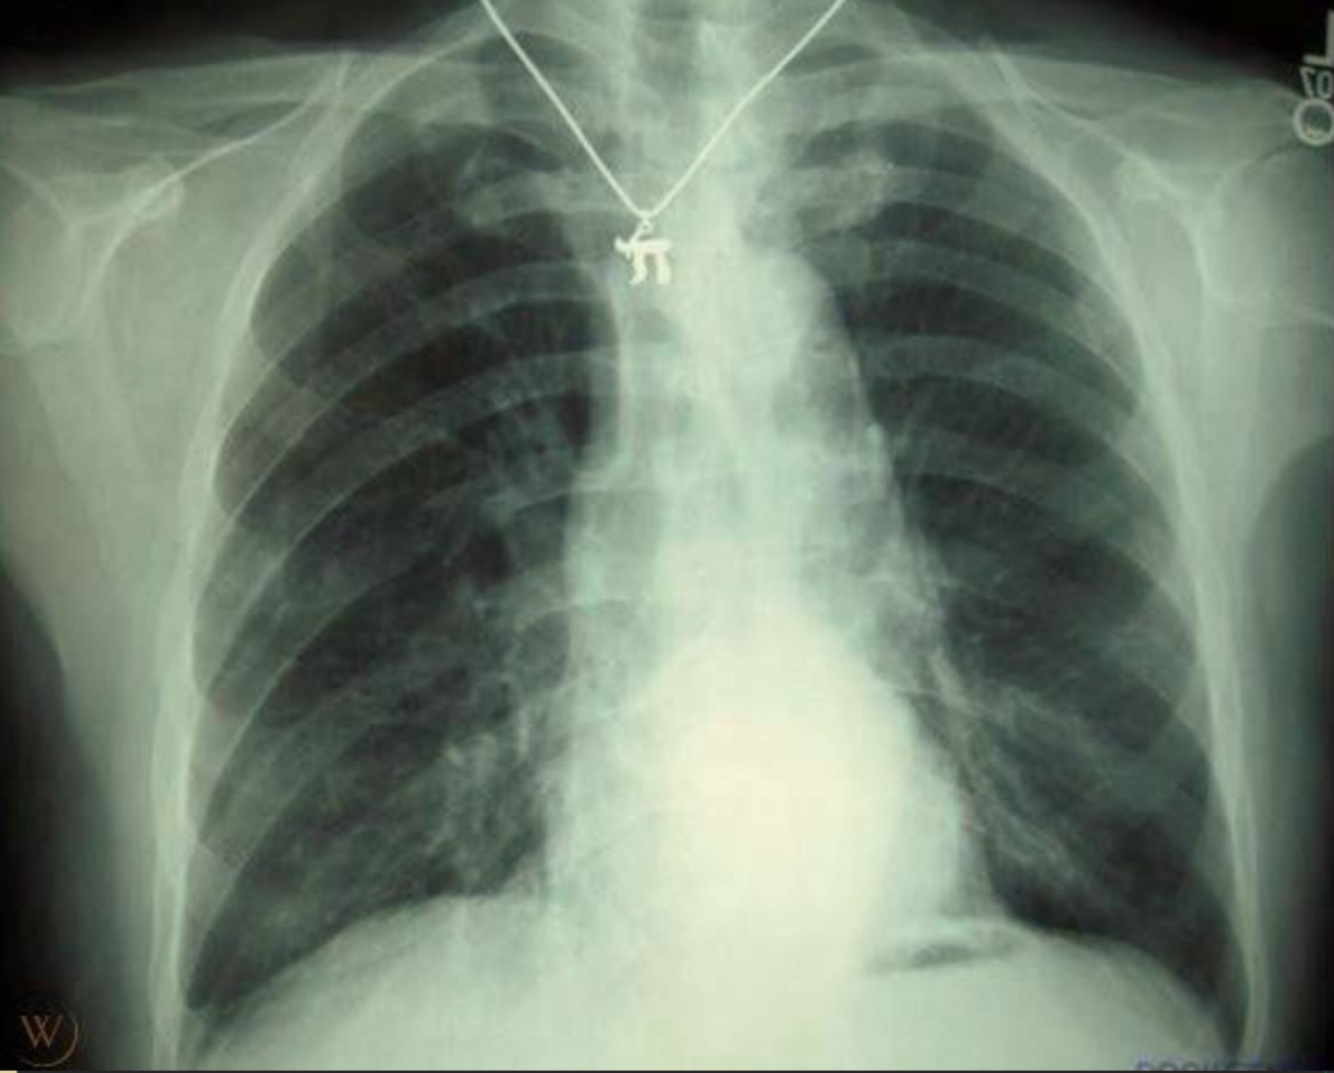

Foreign body: push up bra